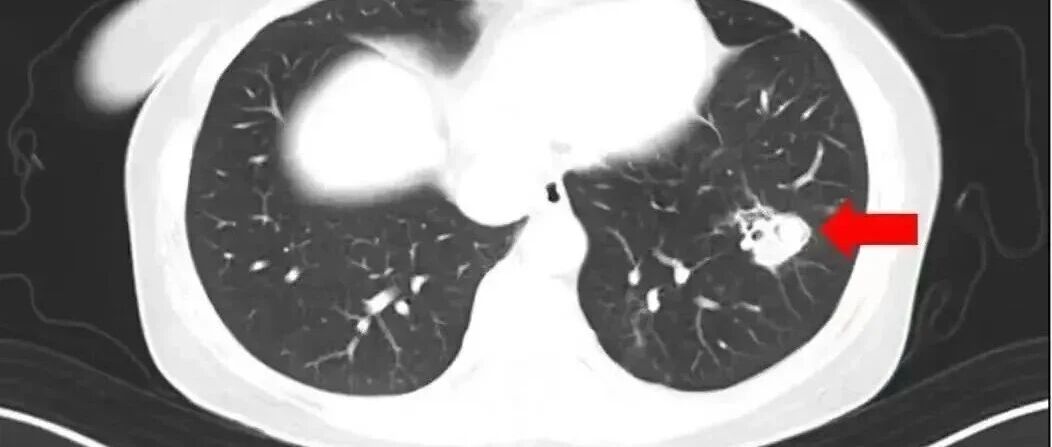

2025年1月,江苏扬州的张大爷为迎接春节开始大扫除,清扫过程中不慎吸入大量灰尘和霉菌孢子,导致哮喘发作。张大爷随即服用了常备的哮喘治疗药物,可症状反而逐渐加重。经检查,张大爷的肺部出现感染,确诊为肺曲霉病。

北京佑安医院感染综合科主任医师李侗曾介绍,对于免疫力低下的人,吸入了这些真菌,就会发病引起肺部的病变——曲霉肺炎。因为它是通过呼吸道感染的,进入血液后是可以扩散到全身。大脑因为血供最丰富,所以也是真菌最容易侵犯的器官。